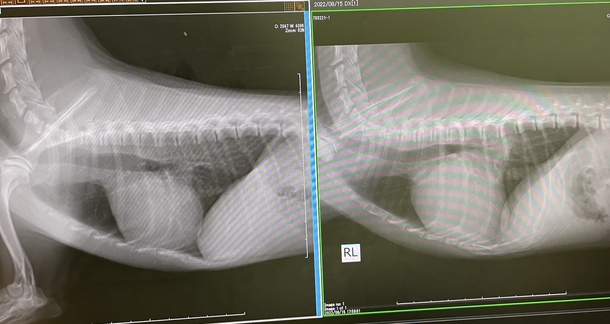

画像は左が現在、右が術前の心臓のレントゲンです。

とっても小さくなっています。